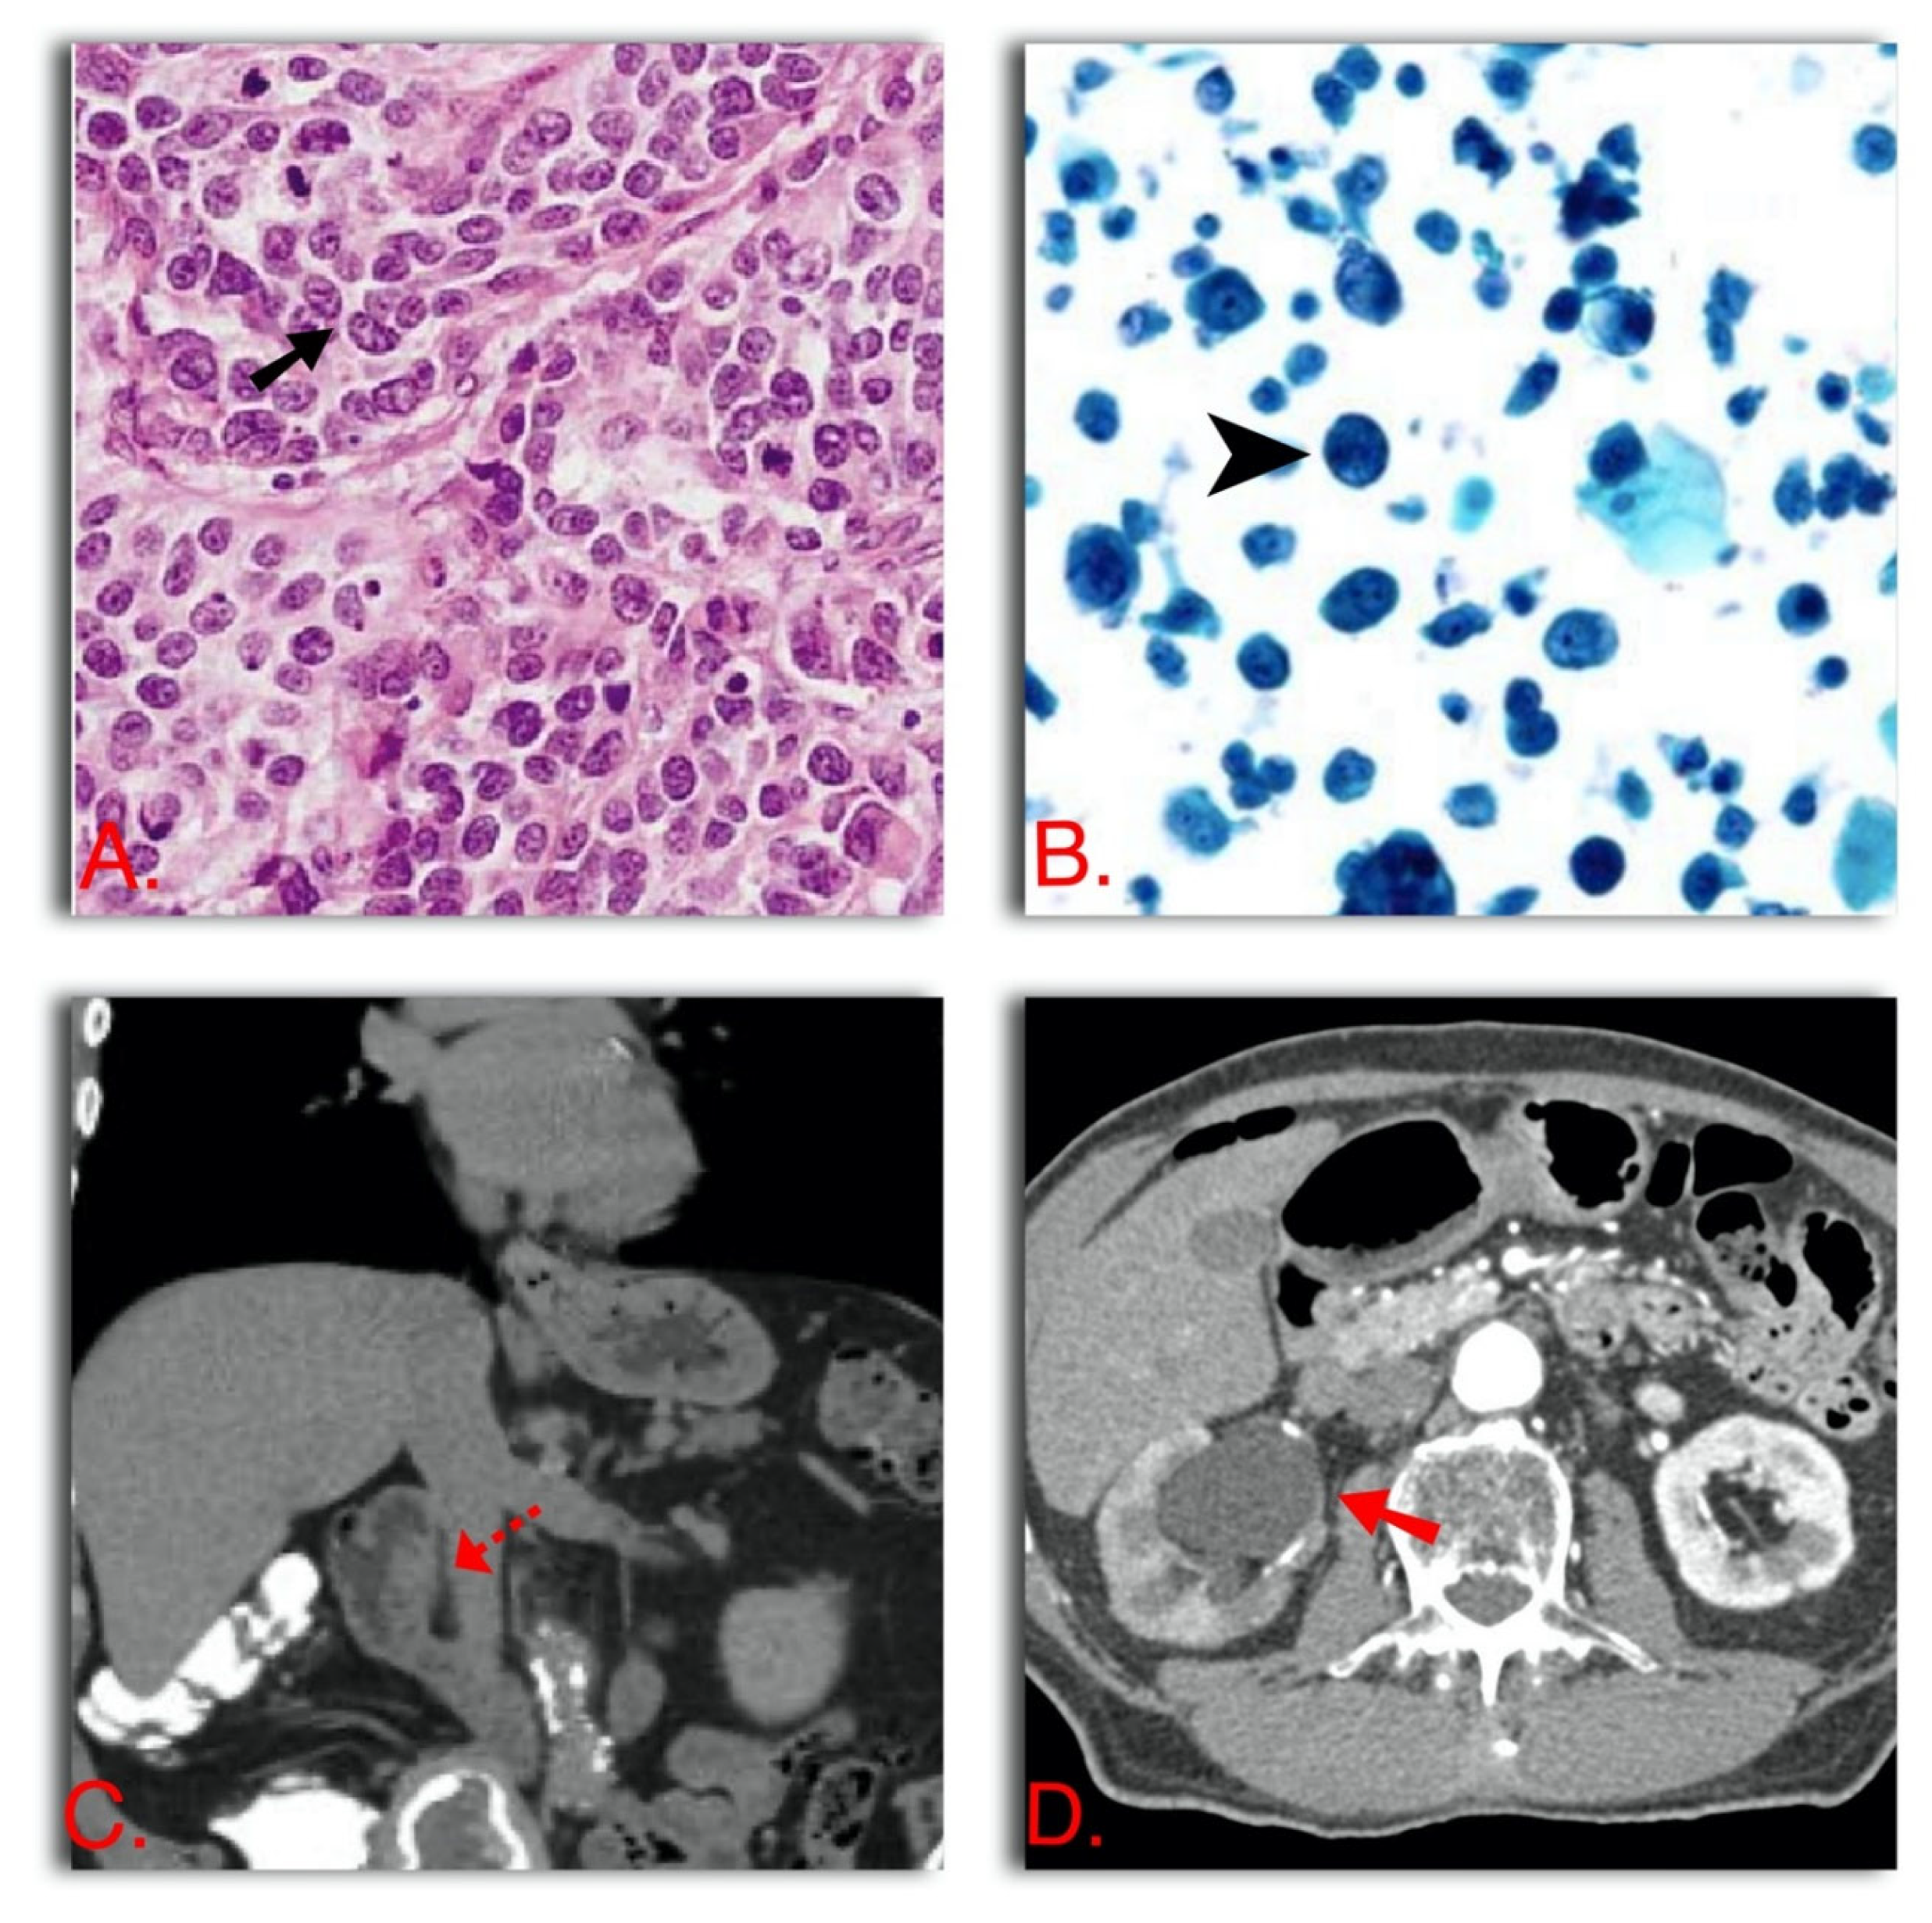

- Ipsilateral hydronephrosis + cHG + positive urine cytology (The three variables combined have 89% PPV and 100% NPV) [9] (Figure 2)

Figure 2. Predictive factors for ≥pT2 UTUC. (A) Hematoxylin-eosin 20× cHG transitional cell carcinoma, diagnosed with URS biopsy of a renal pelvis tumor. (B) Positive urinary cytology (in this case HG). (C) Local invasion of UTUC (periureteric fat extension). (D) Right hydronephrosis secondary to proximal ureteral transitional cell carcinoma. - -

- cHG + cT1 at URS biopsy (PPV 86%) [12]

- Sessile architecture, cHG, ipsilateral hydronephrosis, renal pelvis UTUC, and no multifocality (79% accuracy) [1] (Figure 2)

- Local invasion on imaging (renal sinus fat or periureteric invasion), ipsilateral hydronephrosis, and cHG (71% accuracy) [2] (Figure 2)

We recommend performing LND at the time of RNU if a patient has muscle-invasive disease or in a patient with any of the following characteristics: ipsilateral hydronephrosis, cHG, cT1 at URS biopsy or radiographic signs of renal sinus fat or periureteric fat invasion. If any of the variables are present at preoperative evaluation, the risk of losing the potential benefit of LND is too high; therefore, all these patients should undergo LND.